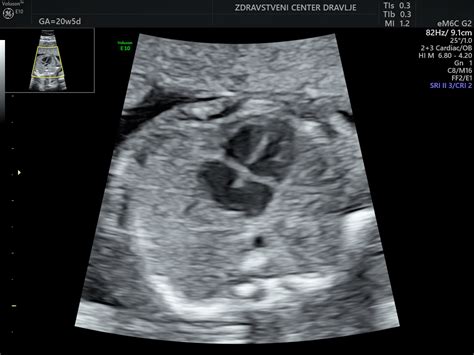

Razvojna displazija kolkov (DDH) je stanje, pri katerem sklep kolka ni pravilno oblikovan. Lahko se pojavi že ob rojstvu ali se razvije v prvih mesecih življenja. Če se DDH ne diagnosticira in zdravi dovolj zgodaj, lahko vodi do kronične bolečine, omejene gibljivosti in celo do prezgodnje osteoartritisa kolka. Ultrazvok je varna, neboleča in učinkovita metoda za zgodnje odkrivanje te težave, saj omogoča vpogled v strukturo kolčnega sklepa, ne da bi pri tem izpostavljali dojenčka škodljivemu sevanju. Zgodnja diagnoza omogoča začetek zdravljenja, ki je pogosto zelo uspešno, zlasti če se prične v prvih mesecih otrokovega življenja.

V dispanzerju v Kranju izvajajo kontrolne preglede po odpustu iz porodnišnice ter prvi preventivni pregled novorojenčka, ki vključuje tudi prvi in kontrolni ultrazvok kolkov dojenčkov. Pomembno je vedeti, da elektronsko naročanje ni namenjeno nujnim primerom. Če imate vprašanja ali dvome glede zdravja vašega dojenčka, se vedno obrnite neposredno na zdravstveno osebje.